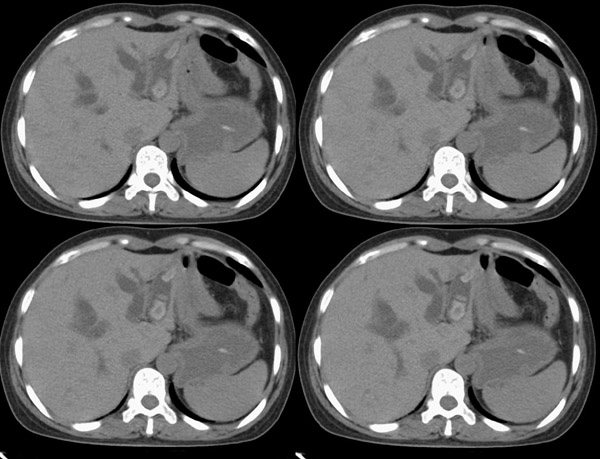

局部1mm薄层重建: